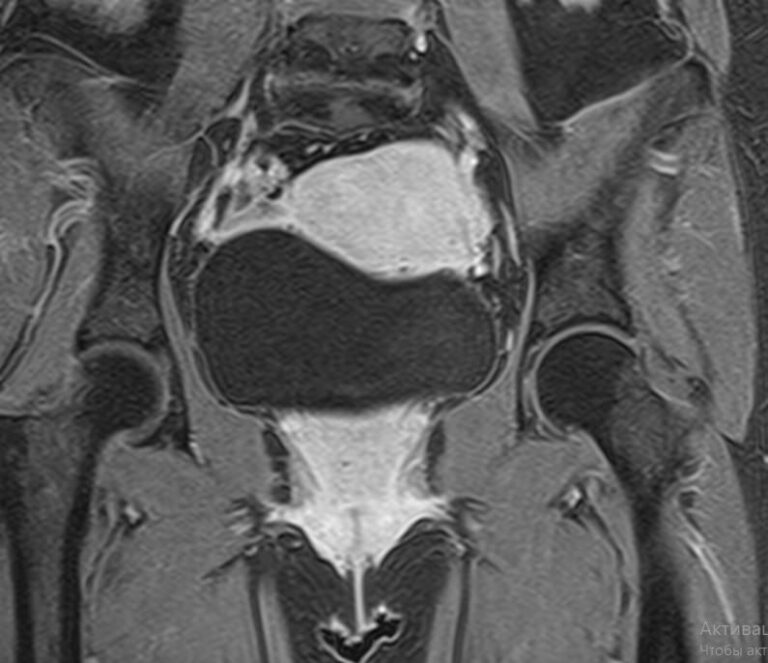

Магнитно-резонансная томография органов малого таза включает в себя исследование женских половых органов (матка, яичники), мужских половых органов (предстательная железа, семенные пузырьки, семявыносящие протоки), мочевого пузыря с мочеточниками, прямой кишки, тазовой брюшины, лимфатических узлов, мягких тканей малого таза.

В нашей клинике исследование выполняется на современном высокопольном томографе экспертного класса TOSHIBA VANTAGE TITAN 1,5 Тесла. Высокая индукция магнитного поля обеспечивает повышенную четкость изображений и превосходную детализацию анатомических структур. Аппарат производит сканирование в трех взаимоперпендикулярных плоскостях и послойными срезами с шагом от 1 мм, что позволяет визуализировать структуру органов и тканей малого таза в мельчайших подробностях.

Выполнение МРТ малого таза в стандартном режиме возможно без использования контраста. Однако при подозрении на патологические изменения со стороны органов мужской или женской половой сферы, мочевыделительной системы, прямой кишки или окружающих мягких тканей, обязательным является введение контрастного препарата, имеющего в своем составе металл гадолиний. Степень и характер накопления контрастного препарата в органах и тканях позволяет различать патологические процессы, в том числе, диагностировать опухоли. Это используется для диагностики онкологических заболеваний на ранних стадиях, что имеет решающее значение для жизни и здоровья пациента.